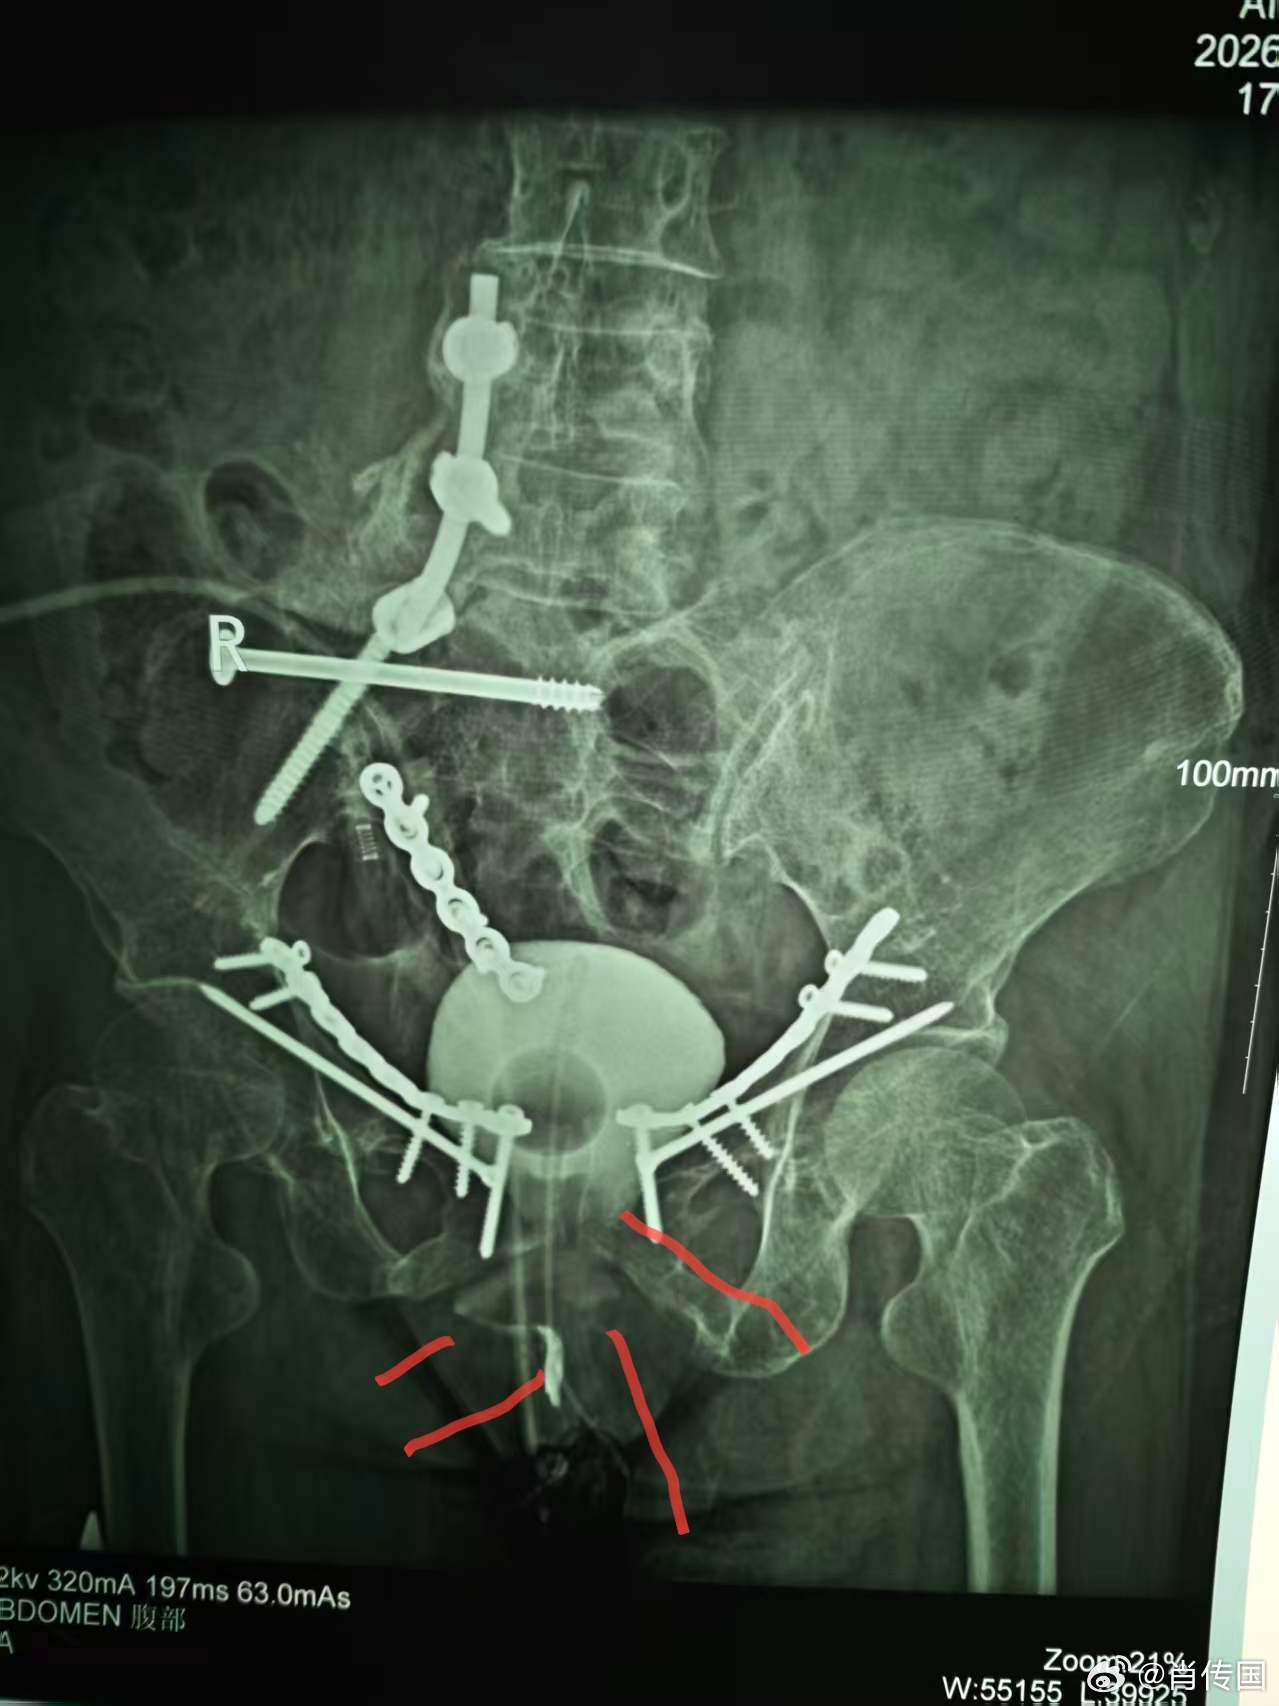

我因肖氏反射弧神经泌尿外科出名,但我的专业实际是整形泌尿外科,作为美国泌尿外科学会Fellow,在最有名的美国泌外整形专科学习工作了二年,回国后除了男女变性没法作,作了无数极端困难泌尿生殖系整形手术,下面这例的复杂困难程度可进入前五吧:介绍一例某省级医院转诊的少见的复杂膀胱瘘,主要给医学同行们参考。7年前因车祸骨盆严重多发骨折,请上海某知名医院骨科专家急会诊手术内固定骨盆。因出血严重,骨盆固定耗时甚长,故仅上尿管未探查处理膀胱等盆腔器官。术后数月出现左腹股沟和会阴部直肠皮肤瘘(耻骨骨拆刺破所致),在外院修复成功。后又发现右会阴大阴唇中上段外侧尿瘘。在外院曾试行经膀胱会阴瘘修补,太过复杂而放弃,转来我院。 经二次手术,治愈。